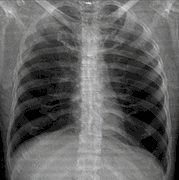

Chest radiograph

A chest radiograph, called a chest X-ray (CXR), or chest film, is a projection radiograph of the chest used to diagnose conditions affecting the chest, its contents, and nearby structures. Chest radiographs are the most common film taken in medicine.

![]() A normal posteroanterior (PA) chest radiograph of someone with Interstitial Pneumonia. Dx and Sin stand for "right" and "left" respectively. | |